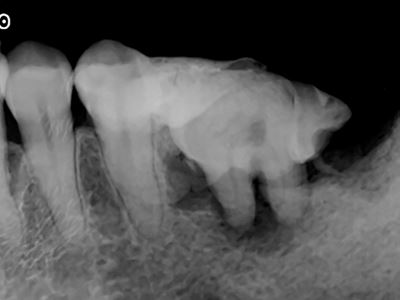

術前X線画像(パノラマ)

術前X線画像:症例2-2

術前X線画像